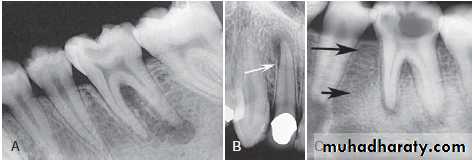

Chronic Osteomyelitis (Chronic diffuse sclerosing osteomyelitis, chronic non-suppurative osteomylitis, Garre’s osteomylitis) :

It is a state of balance in which bone metabolism is tipped toward bone formation producing sclerotic radiographic appearance.

Radiographic features:

Location: *posterior mandible.Periphery: Better defined than the acute phase. In acute exacerbation periphery is radiolucent.

Internal structure: Lesion is more radiopaque and may be equivalent to cortical bone. Small regions of radiolucency may be scattered .

Effects on surrounding structures: New periosteal bone in series of radioqaue lines (onion skin) parallel to the cortical bone surface.

Apical widening of PDL space of non- vital tooth.

Well –defined break in outer cortex (draining fistula).